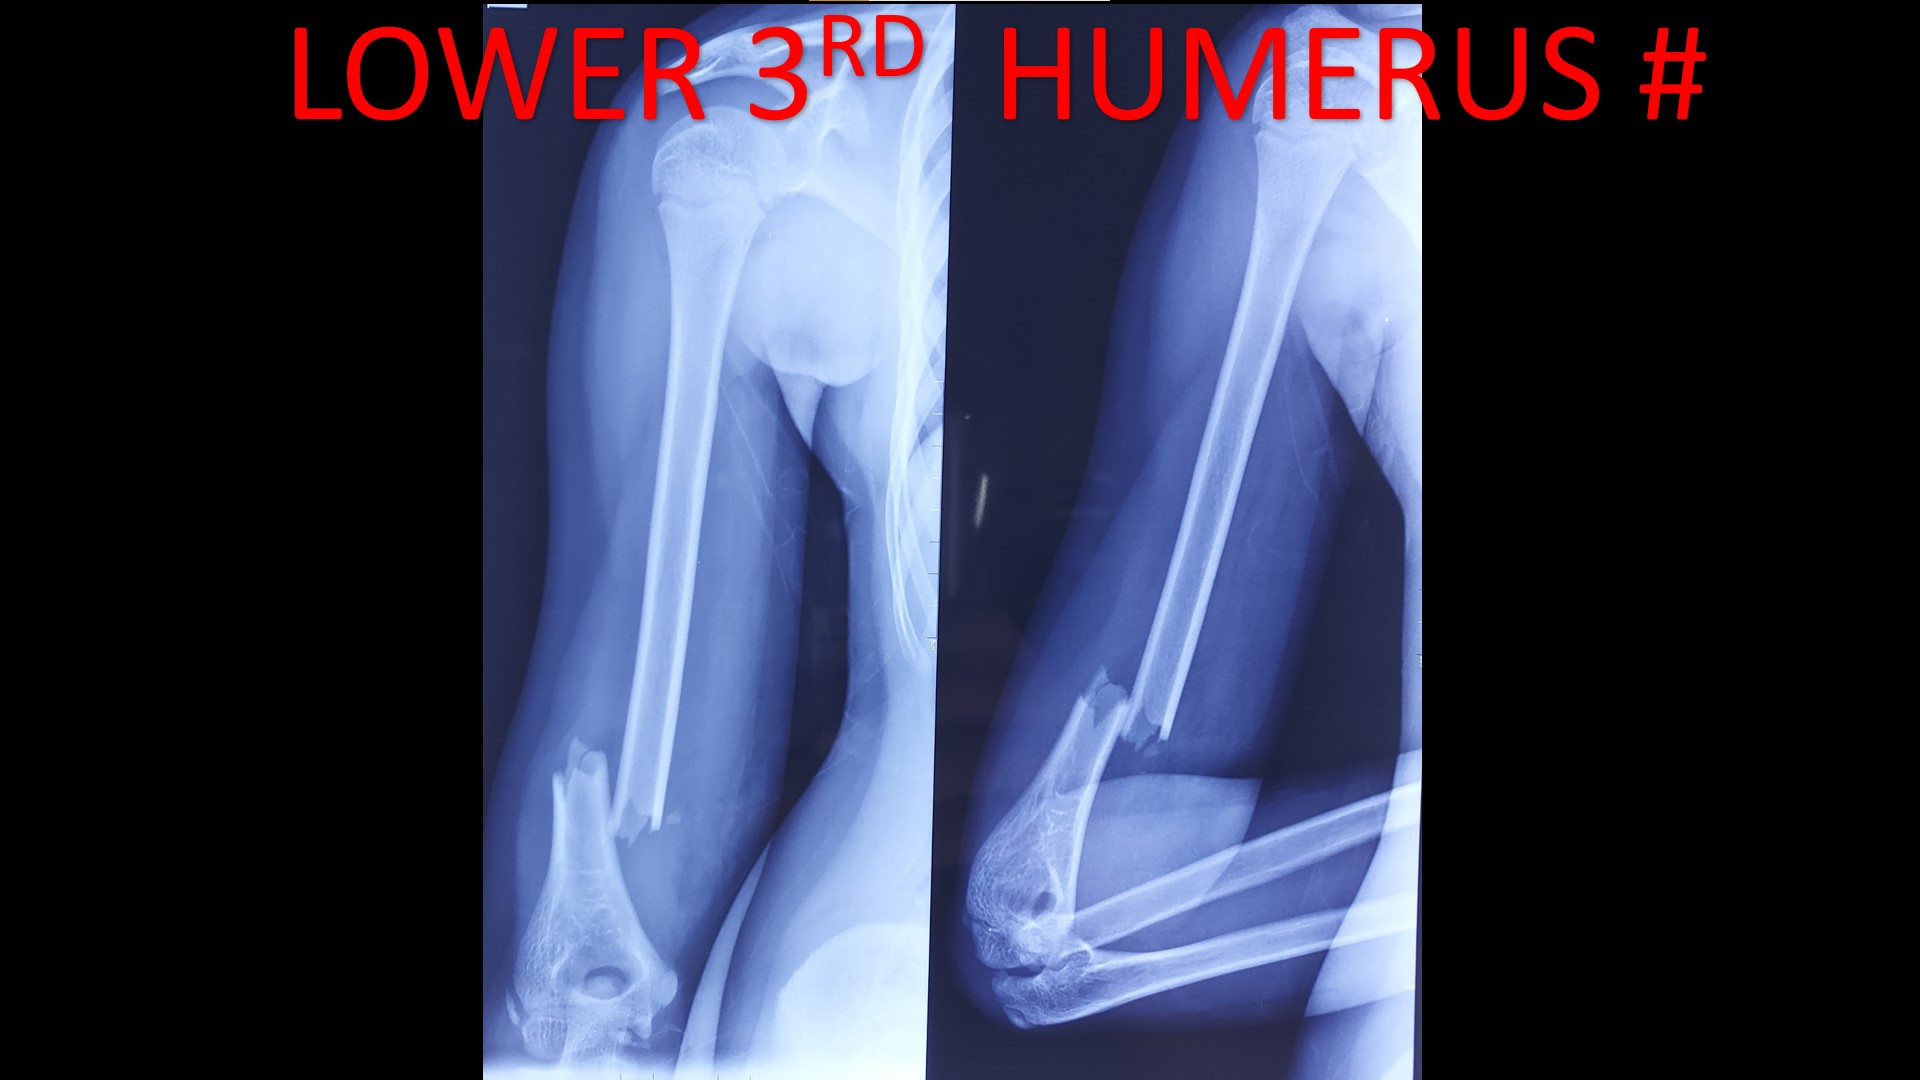

• It can be applied to diaphyseal region adjacent to metaphysis in pediatric fractures, especially distal 3rd arm, forearm and leg fractures.